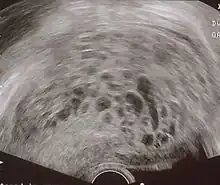

| Histopathologic image of hydatidiform mole (complete type). H&E stain. | |

The diagnosis is strongly suggested by ultrasound (sonogram), but definitive diagnosis requires histopathological examination. On ultrasound, the mole resembles a bunch of grapes ("cluster of grapes" or "honeycombed uterus" or "snow-storm").[14] There is increased trophoblast proliferation and enlarging of the chorionic villi, and angiogenesis in the trophoblasts is impaired.[15]